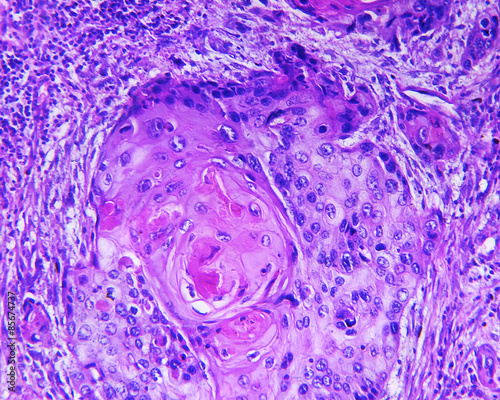

Mikrofotografi - Plakater, Poster, Billeder på lærred